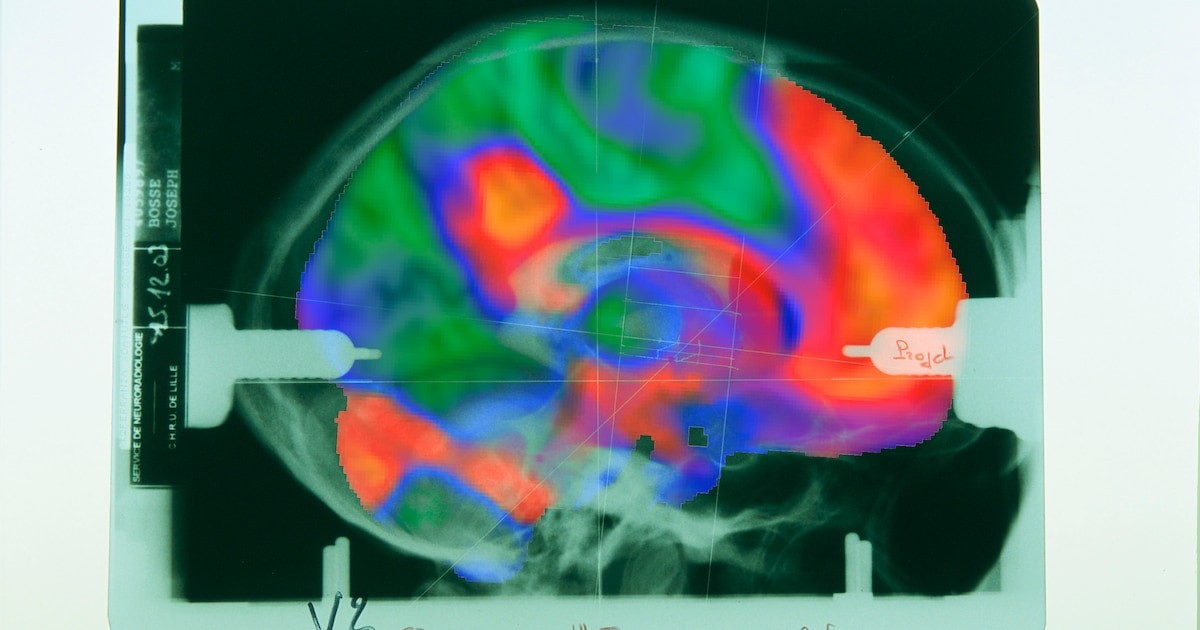

Když neurológ Martijn van den Heuvel před více než rokem porovnával několik publikací o pokročilé technice analýzy lidského mozku, uvědomil si, že všechny obrázky ukazují jedno a to samé. Tato technika, která byla vyvinuta před deseti lety výzkumníky na Harvardově univerzitě, má za úkol zjistit, které mozkové okruhy se podílejí na často nepochopených poruchách, jako jsou migréna, deprese a koktání.

Toto objevování výzkumu otřásá celým oborem. Technika, známá jako „mapování lézíních sítí“, vyvolala ve světě velké nadšení. Podle vědeckého časopisu Scientific American je to technika, která osvětluje dlouho nevyřešené klinické záhady.

Technika ‚mapování lézíních sítí‘ nabývala na popularitě. Vědci objevili mozkové sítě pro více než sto různých psychiatrických a neurologických onemocnění. Slibovali, že pokud lékaři začnou elektricky stimulovat tyto sítě, mohli by zmírnit příznaky pacientů.

Podle nového nizozemského výzkumu se při stanovení těchto individuálních sítí dělá zásadní chyba. Van den Heuvel vysvětluje, že důležité oblasti mozku jsou nadměrně zatíženy v matematických výpočtech, což může vést k tomu, že se opakují stejné sítě, i když to není pravda pro jedno konkrétní onemocnění.